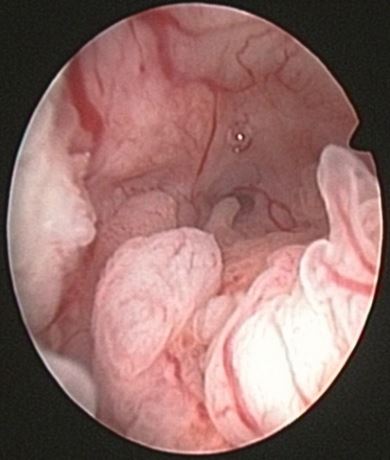

Endometrial hyperplasia is an overgrowth of endometrial glands, with different shapes and sizes, which causes increased endometrial thickness which results in a greather gland / stroma ratio than observed in normal endometrium.

The term endometrial hyperplasia includes different pathologies that have the common feature to increased endometrial thickness. Some of these pathologies have virtually no potential for malignancy while others are clearly premalignant lesions. The pathological diagnosis is the key to the diagnosis of this entity.

2-Complex hyperplasia without atypia: Great growth of the endometrial glands with little stroma. The distribution pattern is irregularly glandular.